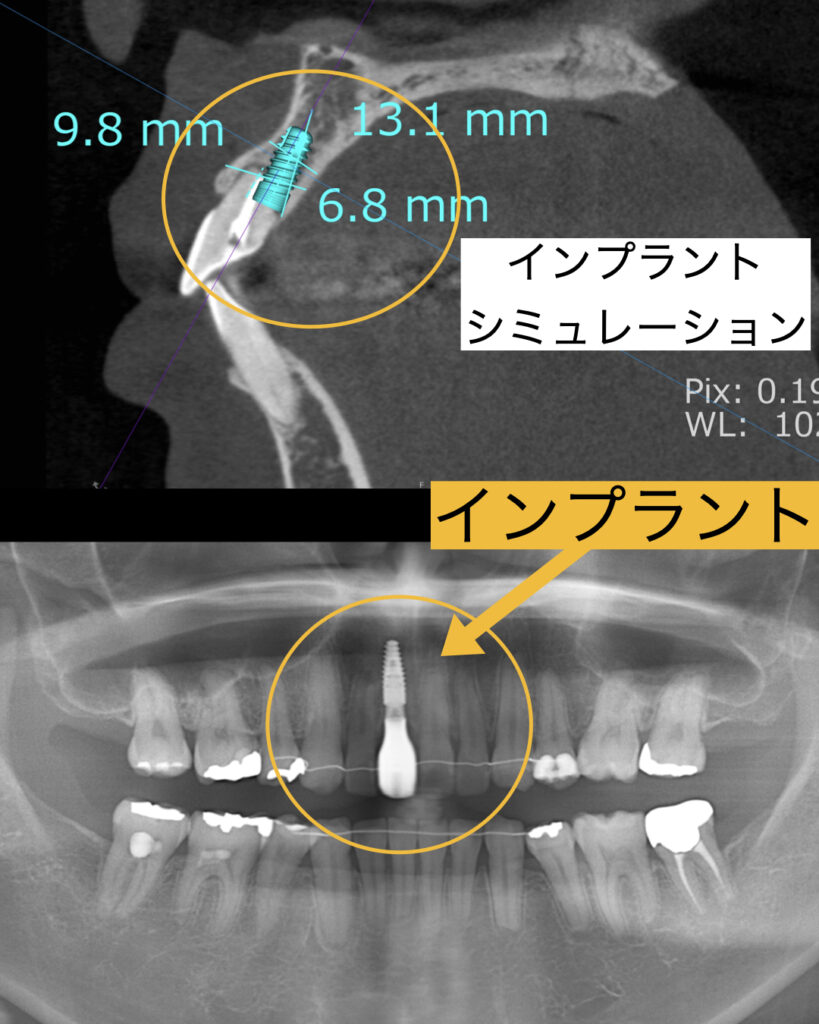

矯正治療中抜けてしまう可能性を十分に説明し、その際はすぐに別の方法で対応することも説明し、患者様の了承のもと矯正治療を行いました。幸い、矯正の最後まで歯はもったものの、治療終了時には根はさらに吸収されグラグラの状態でした。よって、すぐにインプラント治療に移行することにしました。まずはシミュレーションを行い今の歯牙の位置とインプラントの位置を確認し準備を行う